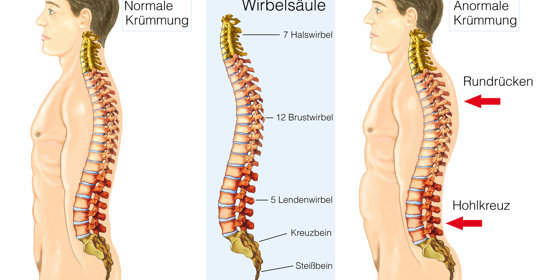

脊椎頭痛的診斷、治療與預防